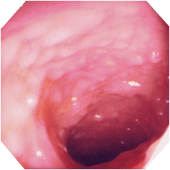

■活動期内視鏡的所見による分類

注12)内視鏡的に観察した範囲で最も所見の強いところで診断しする。 内視鏡検査は前処置なしで短時間で施行し、必ずしも全大腸を観察する必要はない。 棟方昭博:厚生省特定疾患難治性炎症性腸管障害調査研究班 平成9年度研究報告書